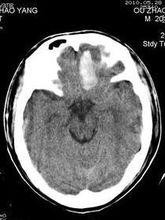

檢查時,可發現患兒面色蒼白、口唇青紫、呼吸快而不規則,有時囟門膨出,頸部強直局部癱瘓、肌張力減低、瞳孔大小不等或有斜視、眼球震顫及眼瞼下垂等。可用B超及CT進行診斷。